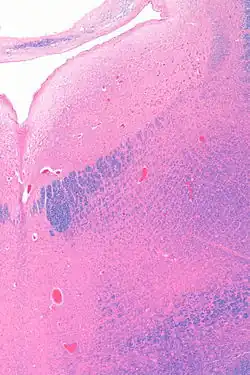

The locus coeruleus (/sɪˈruːliəs/) (LC), also spelled locus caeruleus or locus ceruleus,[1] is a nucleus in the pons of the brainstem involved with physiological responses to stress and panic.[2] It is a part of the reticular activating system in the reticular formation.[3]

Anatomy

The locus coeruleus (LC) is located in the posterior area of the rostral pons in the lateral floor of the fourth ventricle. It is composed of mostly medium-size neurons. Melanin granules inside the neurons contribute to its blue colour. Thus, it is also known as the blue nucleus, or the nucleus pigmentosus pontis (heavily pigmented pontine nucleus).[5] The neuromelanin is formed by the polymerization of norepinephrine and is analogous to the black dopamine-based neuromelanin in the substantia nigra.

In adult human males,[a] the locus coeruleus has 22,000 to 51,000 total pigmented neurons that range in volume from 31,000 to 60,000 μm3.[6]